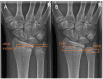

Osseous deformities in children arise due to progressive angular growth or complete physeal arrest. Clinical and radiological alignment measurements help to provide an impression of the deformity, which can be corrected using guided growth techniques. However, little is known about timing and techniques for the upper extremity. Treatment options for deformity correction include monitoring of the deformity, (hemi-)epiphysiodesis, physeal bar resection, and correction osteotomy. Treatment is dependent on the extent and location of the deformity, physeal involvement, presence of a physeal bar, patient age, and predicted length inequality at skeletal maturity. An accurate estimation of the projected limb or bone length inequality is crucial for optimal timing of the intervention. The Paley multiplier method remains the most accurate and simple method for calculating limb growth. While the multiplier method is accurate for calculating growth prior to the growth spurt, measuring peak height velocity (PHV) is superior to chronological age after the onset of the growth spurt. PHV is closely related to skeletal age in children. The Sauvegrain method of skeletal age assessment using elbow radiographs is possibly a simpler and more reliable method than the method by Greulich and Pyle using hand radiographs. PHV-derived multipliers need to be developed for the Sauvegrain method for a more accurate calculation of limb growth during the growth spurt. This paper provides a review of the current literature on the clinical and radiological evaluation of normal upper extremity alignment and aims to provide state-of-the-art directions on deformity evaluation, treatment options, and optimal timing of these options during growth.